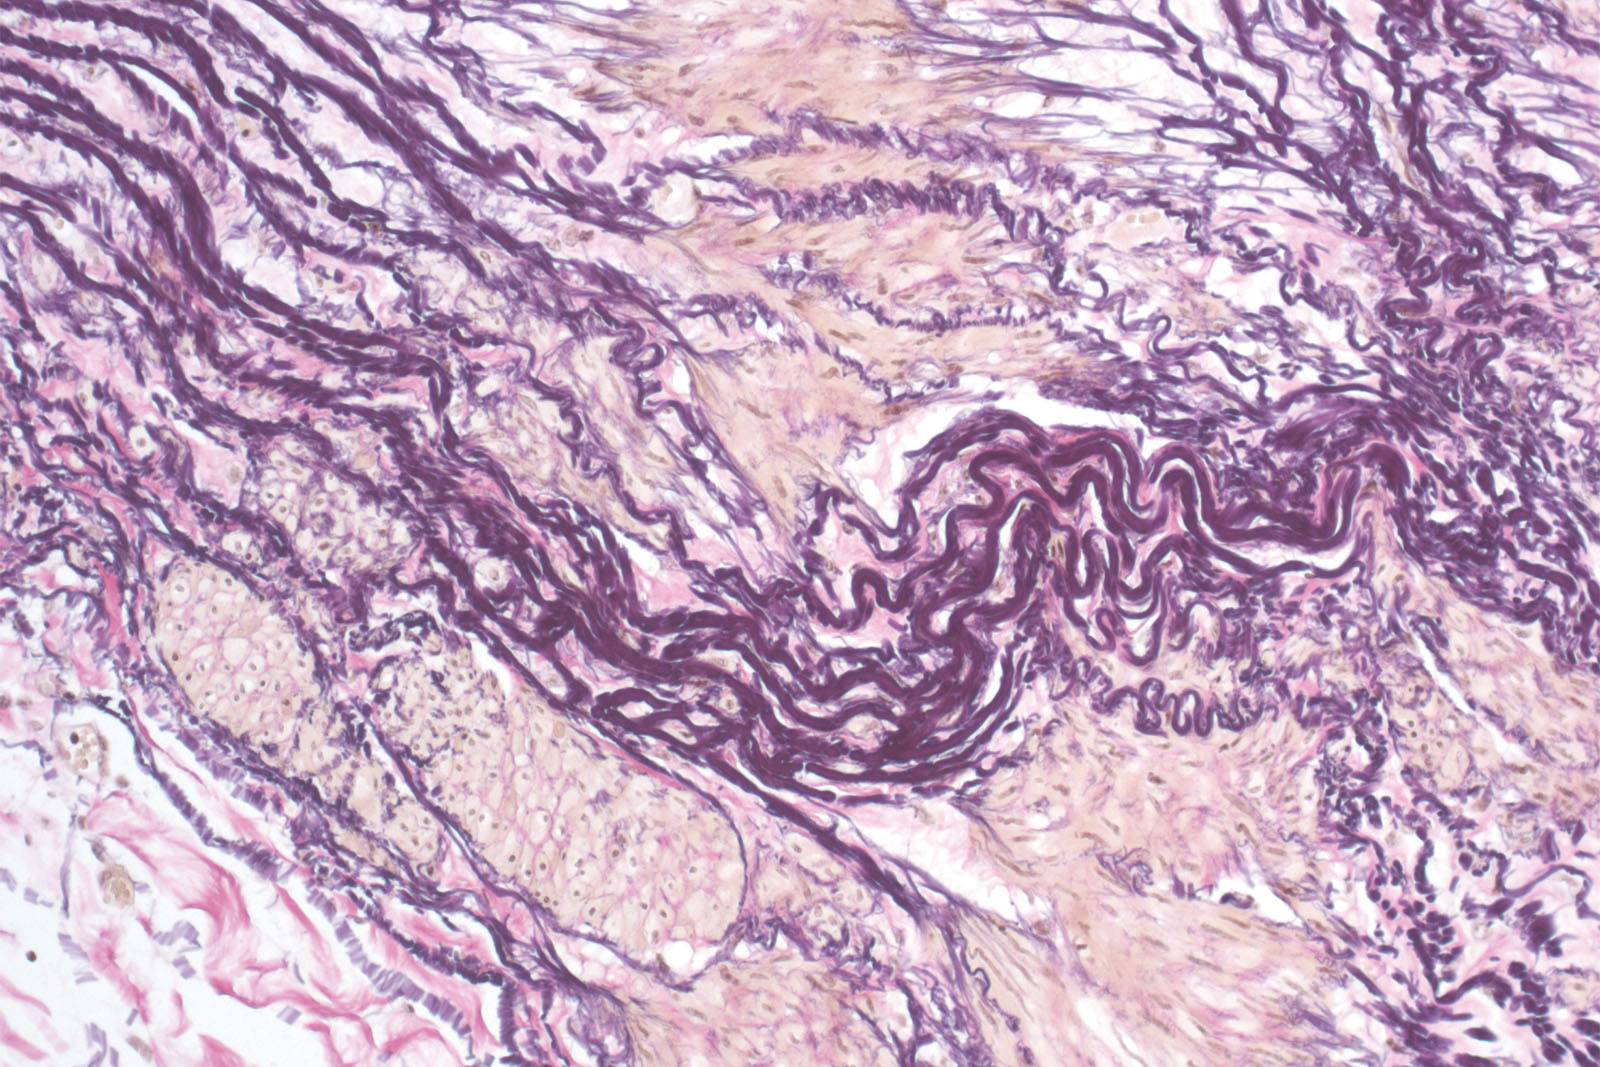

Elastica-Van Gieson kit is used for staining elastin, connective tissue and collagen. Elastic fibers consist of elastin polymers and elastic microfibrils that make up a 3D network in an extracellular matrix inside connective tissue (skin, elastic cartilage, vascular walls, lung tissue and in vocal cords). Unlike standard histology stains, Weigert Van Gieson reagent (known as a resorcin-fuchsin reagent) displays selective differentiation of tissue samples, even in the early phase of the disease. When using the Elastica-Van Gieson kit, the sections are first treated with Resorcine Fuchsin reagent. The positively charged hydrophobic resorcin-fuchsin dye is present in large amounts and it is deposited owing to electropolarity to acid, negatively charged shells of elastic fibers. After differentiation in diluted alcohol or rinsing in tap water, the nuclei are stained with acid-fast Weigert hematoxylin. The last phase of staining is staining with Fuchsin Acid Van Gieson reagent that contains two dyes (acid fuchsin, picric acid) that simultaneously stain different tissue structures. Acid fuchsin stains collagen fibers intensive red while picric acid stains muscle fibers, erythrocytes and glial fibers yellow. Sections are optimally stained in a short period of time by using a rapid staining method.